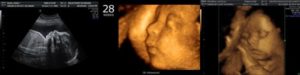

В настоящее время на сроке 28 недель все чаще стали использовать 3d-УЗИ. При нем женщины могут рассмотреть более точную картинку своего малыша. Исследование позволяет оценить все показатели и их соответствие сроку беременности.

На этом сроке уже можно проводить 3D и 4D УЗИ. При этом женщина получает на руки фото, на котором лицо ребенка проявляется максимально отчетливо. В дальнейшем разглядеть его будет гораздо труднее.

Как ребенок выглядит на УЗИ

На 28 неделе ребенок развит уже хорошо и с каждым днем становится все более похожим на новорожденного. Благодаря подвижным суставам он шевелит ногами и руками, сгибает и разгибает пальцы. Черты лица и пропорции тела начинают меняться.

Плод может закрывать и открывать глаза, у него растут ресницы. Благодаря особому пигменту волосы и брови темнеют. Пушковой волос исчезает с туловища, оставаясь лишь на руках и плечах. К 28 неделе у ребенка скапливается жировая ткань, из-за чего он выглядит не слишком худым.

Как выглядит ребенок на УЗИ

Плод умеет открывать глазки, сжимать пальчики в кулачки, способен слышать мамин голос. У малыша появляются реснички, волосы и брови. Морщинки на коже разглаживаются из-за набора жировой ткани. Вес ребенка на этом сроке около 1,1–1,2 кг.

Мозг уже оформился, имеет борозды, извилины. Развиваются корковые структуры, отвечающие за слух, вкус и обоняние.

Сформировались половые органы, при желании женщины смотрят пол ребенка. У мальчиков после 28 недель беременности происходит опускание яичек в мошонку.